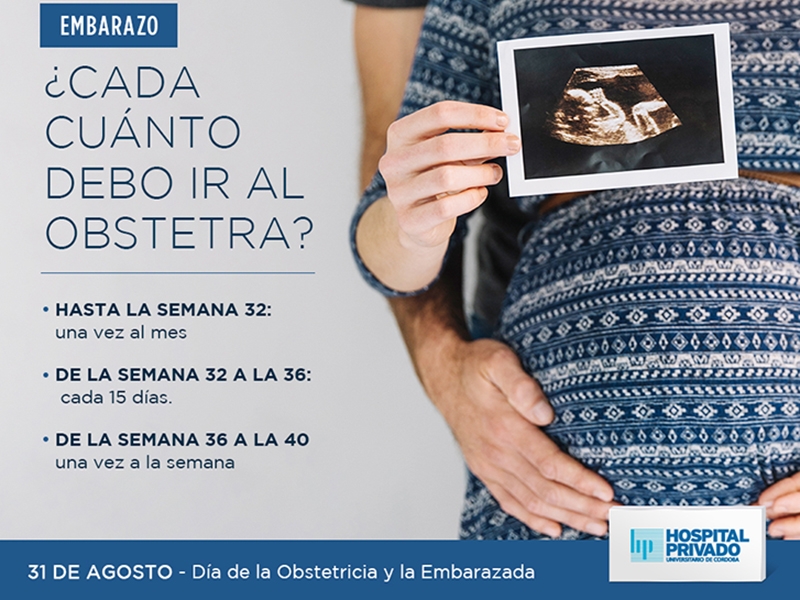

Control Prenatal minsal 2015

Control prenatal del embarazo pruebas analiticas y ecografias

El control del embarazo semana a semana